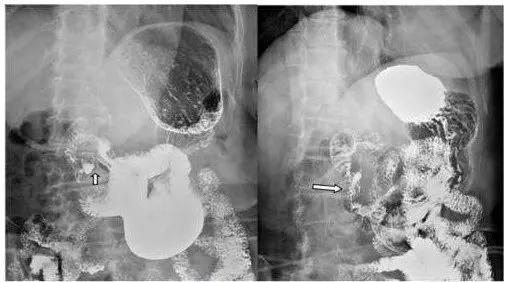

十二指肠球部溃疡X线影像

A 充盈相示:大弯侧腔外龛影;B 双对比相示:前后壁两个溃疡相吻